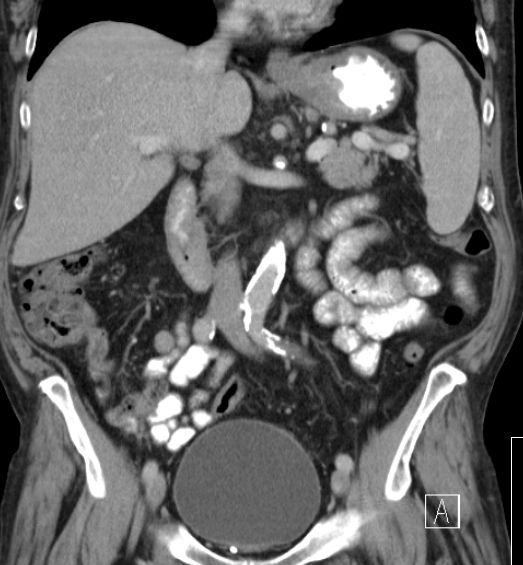

| große Kurvatur | Magenkarzinom an der großen Kurvatur mit Lymphknotenmetastasen. Ausgedehnte Lebermetastasen.![]() |